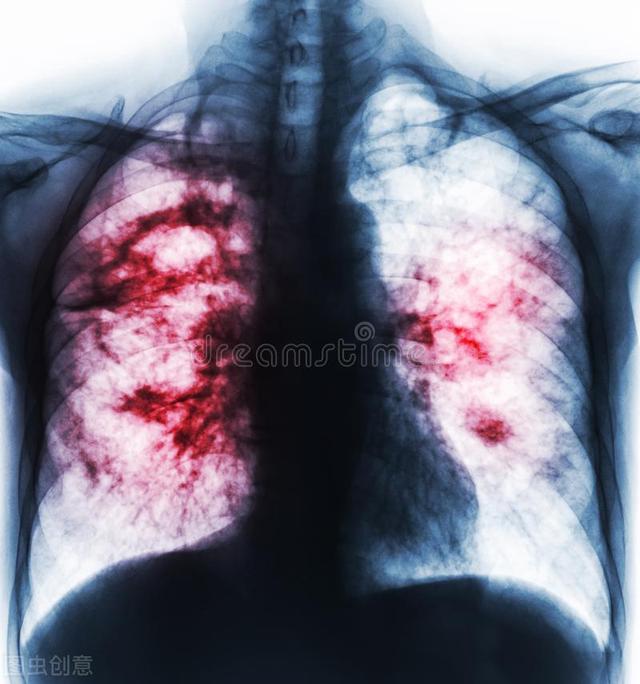

毛霉菌病的特征是以菌丝侵犯血管导致组织梗死和坏死,疾病进展通常很快。

毛霉菌通常会侵犯以下部位,引起感染:鼻-眼眶-大脑、肺部、胃肠道、皮肤、肾、中枢神经系统、或者广泛的播散在身体各器官组织。